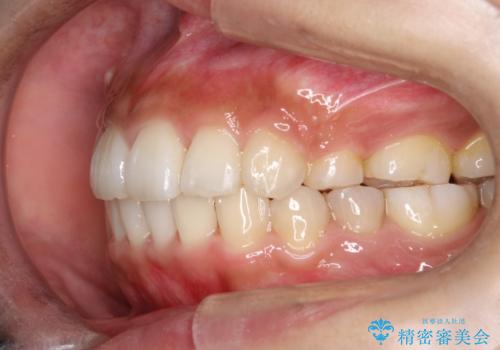

骨格的要因を背景にもつ不正咬合のため、歯列矯正単独での改善は困難と判断しましたが、患者さんとの相談の結果、歯列矯正単独で可能なところまで一緒に頑張りましょうということで、治療をすすめました。

シビアな叢生や開咬も改善することができ、想像以上の改善に時間をかけた甲斐があったと満足していただけました。